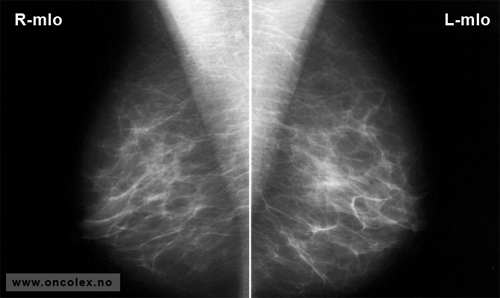

Eksempler på mammografibilder

Mammografi vertikalt plan (skråprojeksjon) av begge bryst. Ingen sykelige funn.